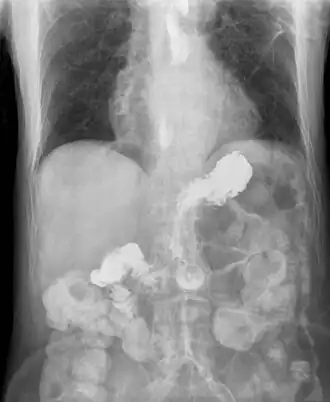

Os fatores de risco incluem obesidade, gravidez, fumar, hérnia do hiato e alguns medicamentos.[1] Os medicamentos envolvidos mais comuns são anti-histamínicos, bloqueadores dos canais de cálcio, antidepressivos e indutores do sono.[1] A doença é causada por uma disfunção do esfíncter esofágico inferior, a união entre o estômago e o esófago, que não encerra por completo.[1] Em pessoas que não melhoram com medidas de tratamento simples, podem ser necessários métodos complementares de diagnóstico, como endoscopia digestiva alta, radiografias com contraste, phmetria esofágica ou manometria esofágica.[1]

Nos casos com sintomas típicos em que a endoscopia é normal, a pH-metria esofágica costuma fazer o diagnóstico. O esfíncter esofágico inferior (EEI) é localizado por manometria e então um cateter com sensor de pH é inserido por via nasal até o esôfago, registrando o pH esofágico durante um período de 24 horas.